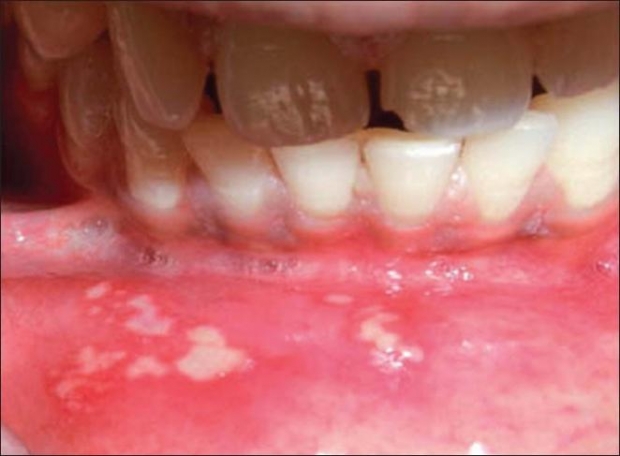

афтозный стоматит — считается инфекционно-аллергическим заболеванием, склонным к хроническому течению. Для него характерно образование эпителиального некроза (так называемые афты с ярко-красным ободком);

кандидозный стоматит — слизистая рта становится сухой, затем на ней образуется налет творожистой консистенции, который легко удаляется ватным тампоном. После удаления под налетом может появиться кровь.